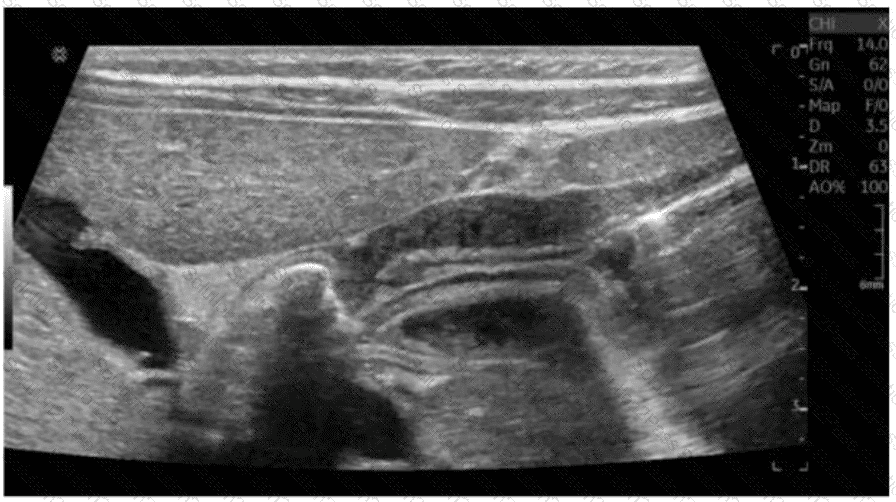

Which finding is demonstrated in this image?